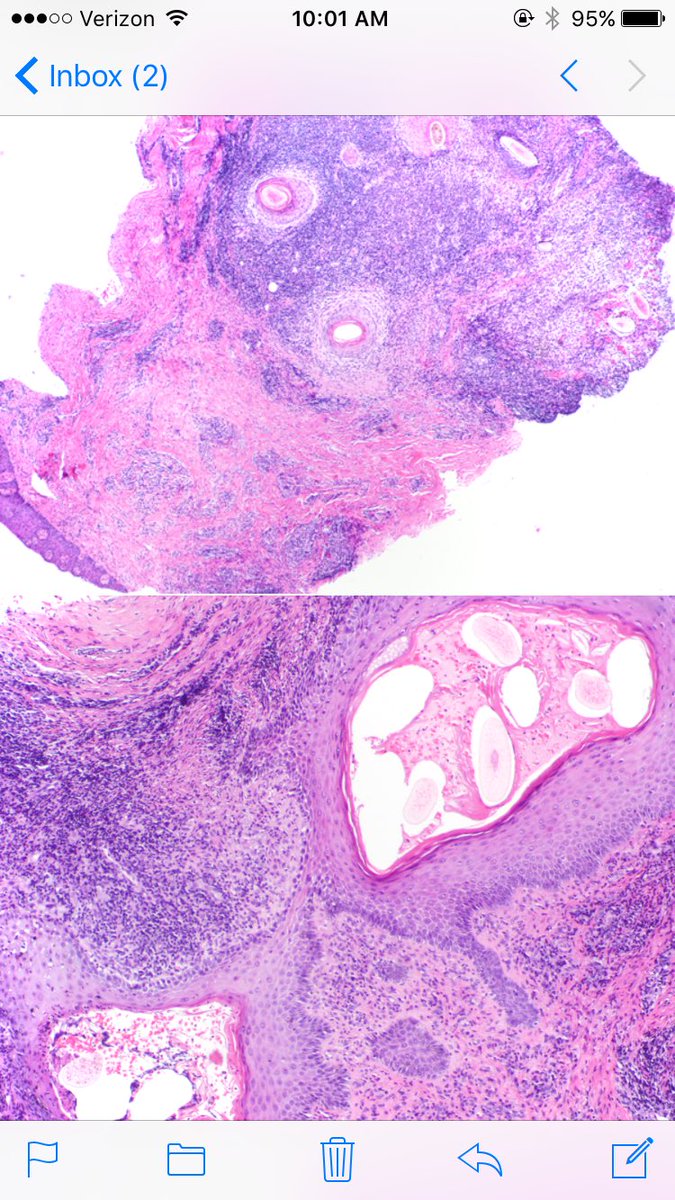

Follic. decalvans: not specific disease--PATTERN of very inflam cicat alop, usually from CCCA or LPP. Polytrichia (fused infundibula common)

LenSperling's tweet image. Follic. decalvans: not specific disease--PATTERN of very inflam cicat alop, usually from CCCA or LPP. Polytrichia (fused infundibula common)